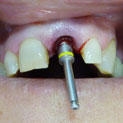

En estos casos han sido tratados con la filosofía de all-at-once, en la

misma sesión: